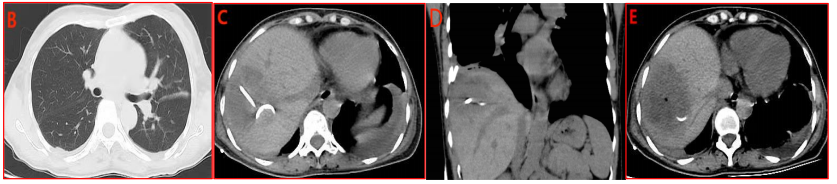

血生化检查提示转氨酶增高、低蛋白血症,予保肝、输人血白蛋白等治疗。12月5日患者体温恢复正常(图4A)。治疗2周后复查CT:右侧胸腔引流管置入,双侧胸腔见少量积液;肝脓肿引流管置入,右肝内约5.9cm×5.1cm低密度区,见小气泡,边界模糊(图4B-E)。

图4. 治疗后体温(部分)变化及CT复查